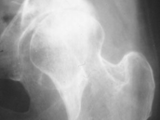

AVN-hips

AVN-hips